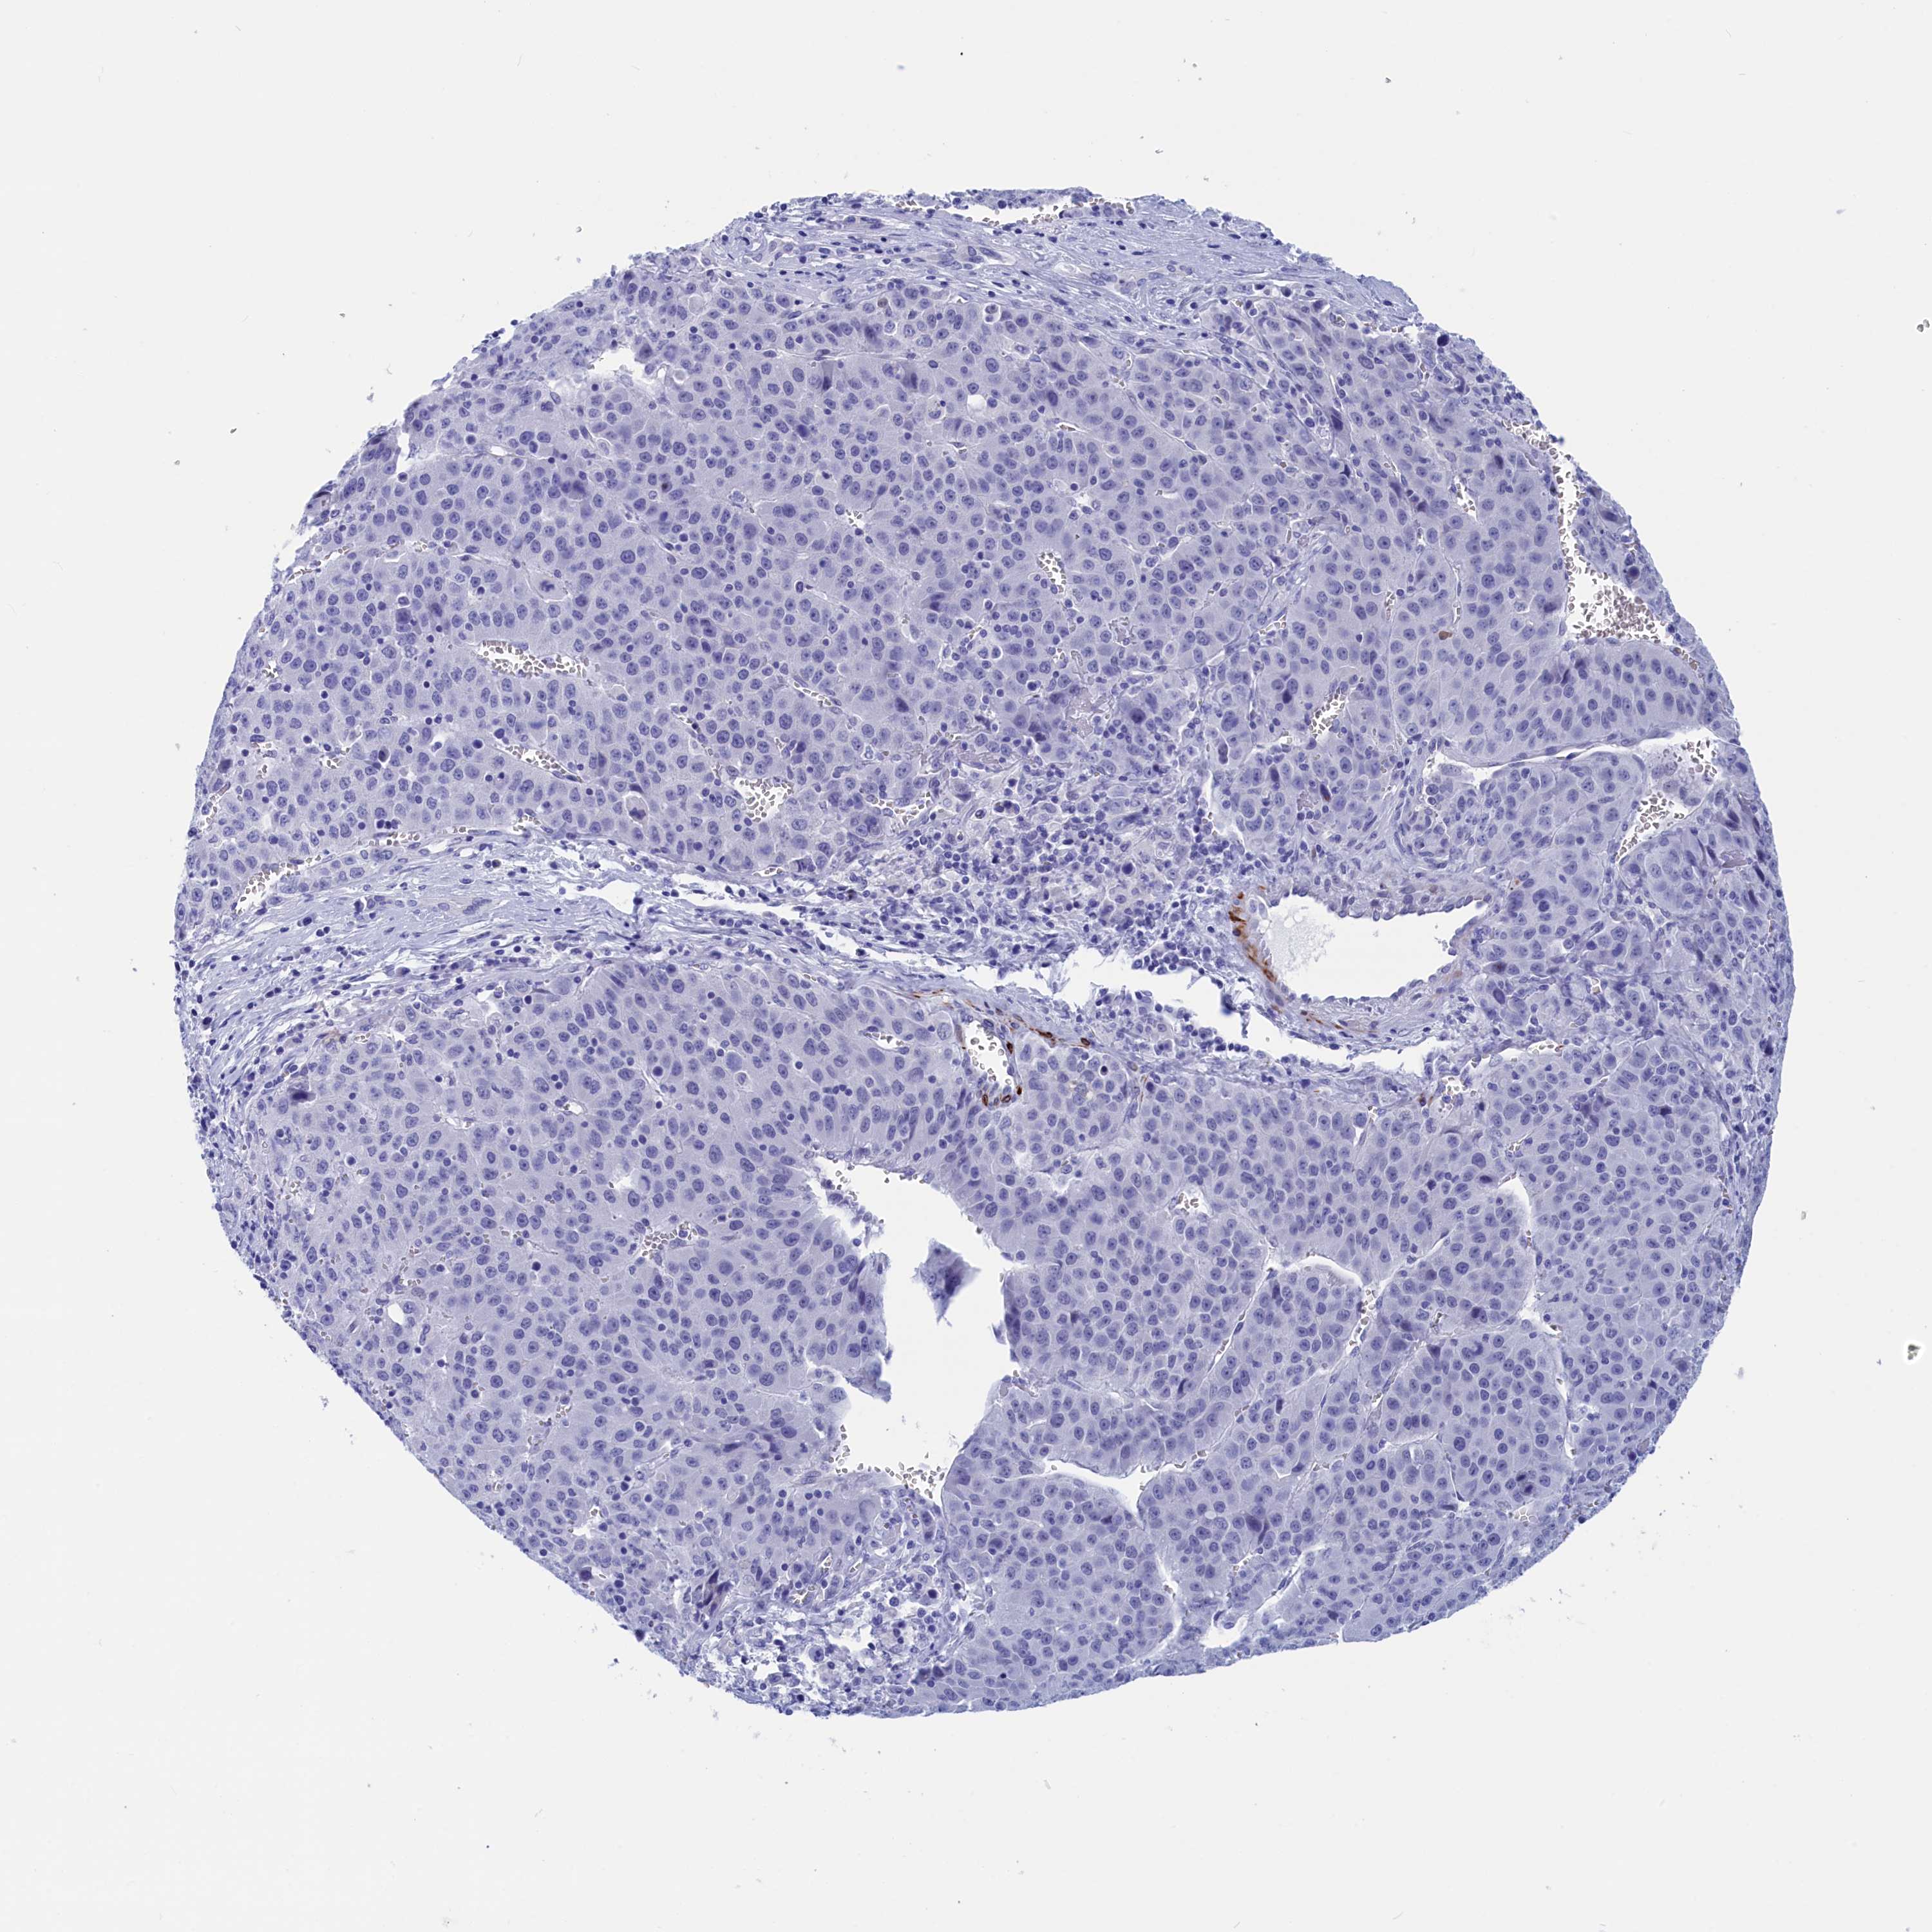

LIVER CANCER - Protein expressioni

A mouse-over function shows sample information and annotation data. Click on an image to view it in a full screen mode. Samples can be filtered based on level of antibody staining by selecting one or several of the following categories: high, medium, low and not detected. The assay and annotation is described here.

Note that samples used for immunohistochemistry by the Human Protein Atlas do not correspond to samples in the TCGA dataset.

Antibody stainingi

Antibody staining in the annotated cell types in the current human tissue is reported as not detected, low, medium, or high, based on conventional immunohistochemistry profiling in selected tissues. This score is based on the combination of the staining intensity and fraction of stained cells.

Each image is clickable and will lead to virtual microscopy that enables deeper exploration of all samples and also displays staining intensity scores, fraction scores and subcellular localization as well as patient and tissue information for each sample.

Antibody HPA042629

Antibody HPA042838

Staining

High

Medium

Low

Not detected

Intensity

Strong

Moderate

Weak

Negative

Quantity

>75%

75%-25%

<25%

None

Location

Nuclear

Cytoplasmic/membranous

Cytoplasmic/membranous,nuclear

Cholangiocarcinoma

Carcinoma, Hepatocellular, NOS